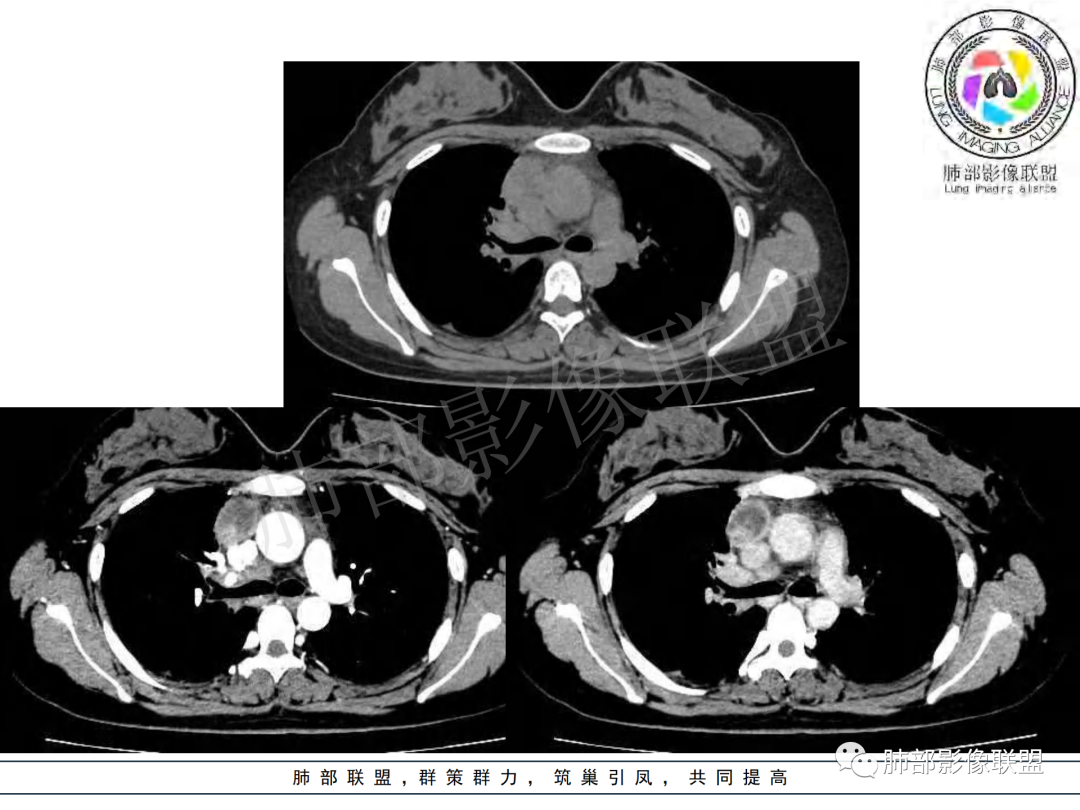

纵隔多组及右侧肺门多发肿大淋巴结,部分融合,不均匀强化,内见斑片状坏死区及环状强化,后者坏死边界尚清晰,肺门区肿大淋巴结与肺组织边界不清,年轻女性,8个月病史,发热首发症状,考虑淋巴结核并向肺内侵及(破溃?),鉴别淋巴瘤

女,20,病程长达8月,发热、胸痛、右侧胸腔积液病史。胸部CT:右肺门旁不规则肿块影,右中间支气管腔内结节,纵隔多发淋巴结肿大;强化不均匀,灶性坏死灶,环形强化;右侧少量胸腔积液并局部肉芽肿样突起。年轻女性,长病程,多部位,考虑慢性炎症,结核?鉴别肿瘤。

年轻女性 大支气管占位恶性三件套 高强化 内部可见无强化区,无强化区与强化区内边界大部分不清晰,类癌、粘表、腺样囊性癌。首先考虑粘表   其次需要鉴别的有结核   这么大片的坏死 结节病可能性小

女性,20岁。高热、畏寒。右肺上叶近肺门区不规则肿块,周围斑点、片小结节影伴肿大淋巴结,肿块包绕并突入右主支气管腔内,增强后肿块不均匀强化,淋巴结环形强化中心低密度,考虑结核。

纵隔肺门及两侧胸膜强化结节,支气管管腔不通畅。结核能解释临床及影像,就是强化有点猛,这个妖怪真不好说。恶性如类癌/高级别黏表/恶性间皮也要考虑。

本例患者,年轻女性,慢性病程,多次抗感染治疗效果不佳,实验室检查示白细胞及中性粒细胞不高,不支持普通细菌感染,虽然肺泡灌洗液X-Pert检测阴性,结合患者胸部CT结核感染亦不能排除,胸部CT主要表现为右侧肺门及纵隔淋巴结肿大,仔细观察不难发现右中间支气管内新生物凸向管腔内,增强扫描,右肺门(10R)及纵隔淋巴结(2R,4R)明显不均匀强化,内部呈不规则低密度无强化区,被周边高强化区包绕(环形强化)的特点,首先应当想到纵隔淋巴结结核诊断。淋巴结分布亦不符合肺部恶性肿瘤迁徙途径。

马尔尼菲篮状菌感染也可表现为多处环形强化肿大淋巴结,但常见于易感人群。